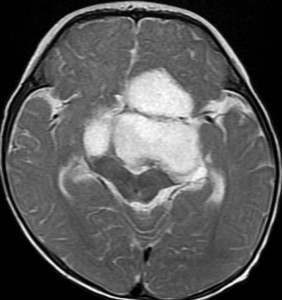

幼児の視路の毛様粘液性星細胞腫です。T2強調画像(左側)で白く高信号に写るのが特徴です。ガドリニウム増強ではまだらになっていますが,均一に真っ白に高信号になることも多いです。乳幼児のものは,ドロドロに柔らかい腫瘍です。

生後7カ月の幼児です。目が揺れるようになり(振り子様眼振)眼科を受診して腫瘍が発見されました。小児脳腫瘍の治療ができる病院へと紹介されました。

1ヶ月後にまたMRI検査がされました。乳児ですから検査にも麻酔が必要です。腫瘍は明らかに大きくなっています。左視神経から視索の腫瘍化が著しいので右側だけかすかに視力が残っているかもしれません。視力は明かりがわかる程度(明暗弁)と評価されました。

乳幼児時期には,病理組織像が毛様粘液性星細胞腫で,MRI T2で均一な高信号になりガドリニウムで強く増強されます。腫瘍の増大速度は速く,稀には髄液播種することもありそれが腫瘍死の原因となることもあります。奏効率の高い化学療法を早く開始する必要があります。